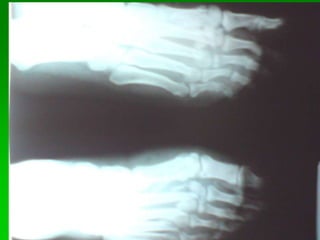

Dedos de los pies (AP.) Dorso plantar

Pie de Frente Posición del paciente

Apoyo dorso plantar

Proyección dorso plantar (pie de frente)

Proyección dorso plantar

 4: NAVICULAR

 5: CUNEIFORME

 6: BASE DEL PRIMER

MEATARSIANO

 7: CUERPO DEL 1º

METATARSIANO

 8: CABEZA DEL 1º

 9: HUESO SESAMOIDEO

 10: FALANGE PROXIMAL

 11: FALANGE MEDIA

 12: FALANGE DISTAL

1. Falange proximal 1 dedo

2. Base primer metatarsiano

3. Diáfisis primer metatarsiano

4. Cabeza primer metatarsiano

5. Huesos sesamoideos

6. Cuneiforme medial

7. Cuneiforme intermedio

8. Cuneiforme lateral

9. Escafoides

10. Tuberosidad del escafoides

11. Cabeza del talo

12. Maléolo lateral

13. Cuboides

14. Calcáneo

Pie AP (dorso plantar)